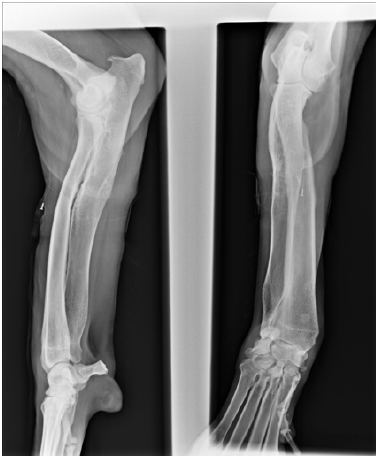

Surgical correction was prescribed; the preoperative planning consisted of developing a customized device to aid the surgeon during surgery. A CT study of both forelimbs was carried out, including the elbow and carpal joints. The dog was placed in sternal recumbency with the forelimbs extended cranially, allowing the carpi and metacarpi toremain in a neutral position. A CT scan was performed in a 2-slice CT scanner witha 1mm gap between cuts, starting in the proximal humerus, and extending to include the metacarpi. The CT findings wereexported to DICOM format, allowing further manipulation, resulting in a 3D reconstruction of the pathological limb (Figure 1B).

The method used to plan the surgery is described by Domenech et al. [10]. This methodallows for correction of angular deformity in a long bone by means ofclosed wedge ostectomies. Thismethod aims to minimize loss of bone length. This methodology only requires the availability of 3-D reconstruction of the diseased bone and the correct definition of the proximal and distal joint planes (Figure 1C). In this case, the 3-D model was obtained by reconstruction information obtained by CT, which was then examined by a surgeon. A surgical plan was formed based on the bone’s anatomical points, which was determined the joint planes.

Figure 1C: In vitro 3D reconstruction of the diseased bone and the correct definition of the proximal and distal joint planes.